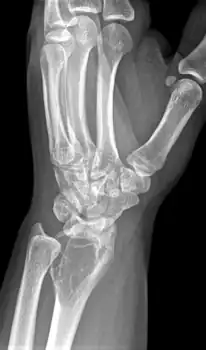

| X-ray of a giant-cell bone tumor in the head of the fourth metacarpal of the left hand | |

On X-ray, giant-cell tumors (GCTs) are lytic/lucent lesions that have an epiphyseal location and grow to the articular surface of the involved bone.[11] Radiologically the tumors may show characteristic 'soap bubble' appearance.[12] They are distinguishable from other bony tumors in that GCTs usually have a nonsclerotic and sharply defined border. About 5% of giant-cell tumors metastasize, usually to a lung, which may be benign metastasis,[13] when the diagnosis of giant-cell tumor is suspected, a chest X-ray or computed tomography may be needed. MRI can be used to assess intramedullary and soft tissue extension.